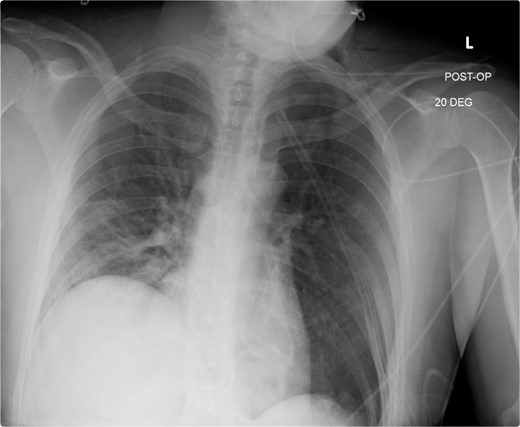

The early postoperative course was unremarkable. The patient reported feeling mild bloating, but was discharged on postoperative Day 1 after removal of a chest tube (Fig. 4). A few hours after discharge from the hospital, he developed dysphagia, progressive abdominal pain, distension, and dyspnea that prompted a return to the hospital. Physical examination revealed tachycardia (132 bpm), mild hypoxia requiring supplemental O2 at 2 L/min via nasal canula, and abdominal distension. Laboratory studies showed WBC of 12 600 cells/μL. A CT scan of the abdomen and pelvis revealed a large, acute organo-axial gastric volvulus without evidence of ischemia, and an intact left hemidiaphragm plication at a similar height to the right hemidiaphragm (Fig. 5). A nasogastric tube was placed with immediate drainage of 1 L of dark bilious fluid with immediate relief of the patient’s symptoms. However, a subsequent film revealed the nasogastric tube projecting toward the upper left chest with presence of colonic haustra (Fig. 6), consistent with acute hemidiaphragm rupture.

Following chest-tube removal, a film was taken, revealing even hemi-diaphragms, which was notably higher than immediate post-operatively, but within normal limits.

Confirmatory abdominal film for nasogastric tube placement demonstrating acute elevation in the left hemidiaphragm, 90-min after the CT, identifying the gastric volvulus.